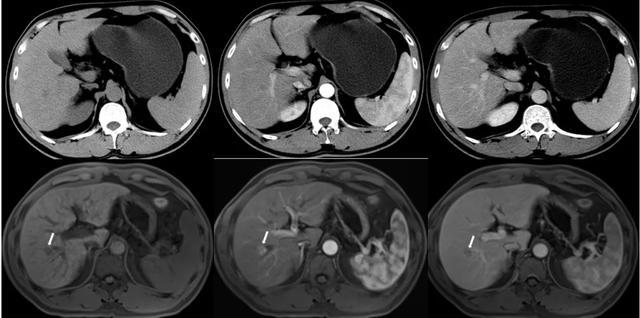

(▲腹部增强MRI清楚显示肝癌的影像特征,但增强CT对病灶显示不清)